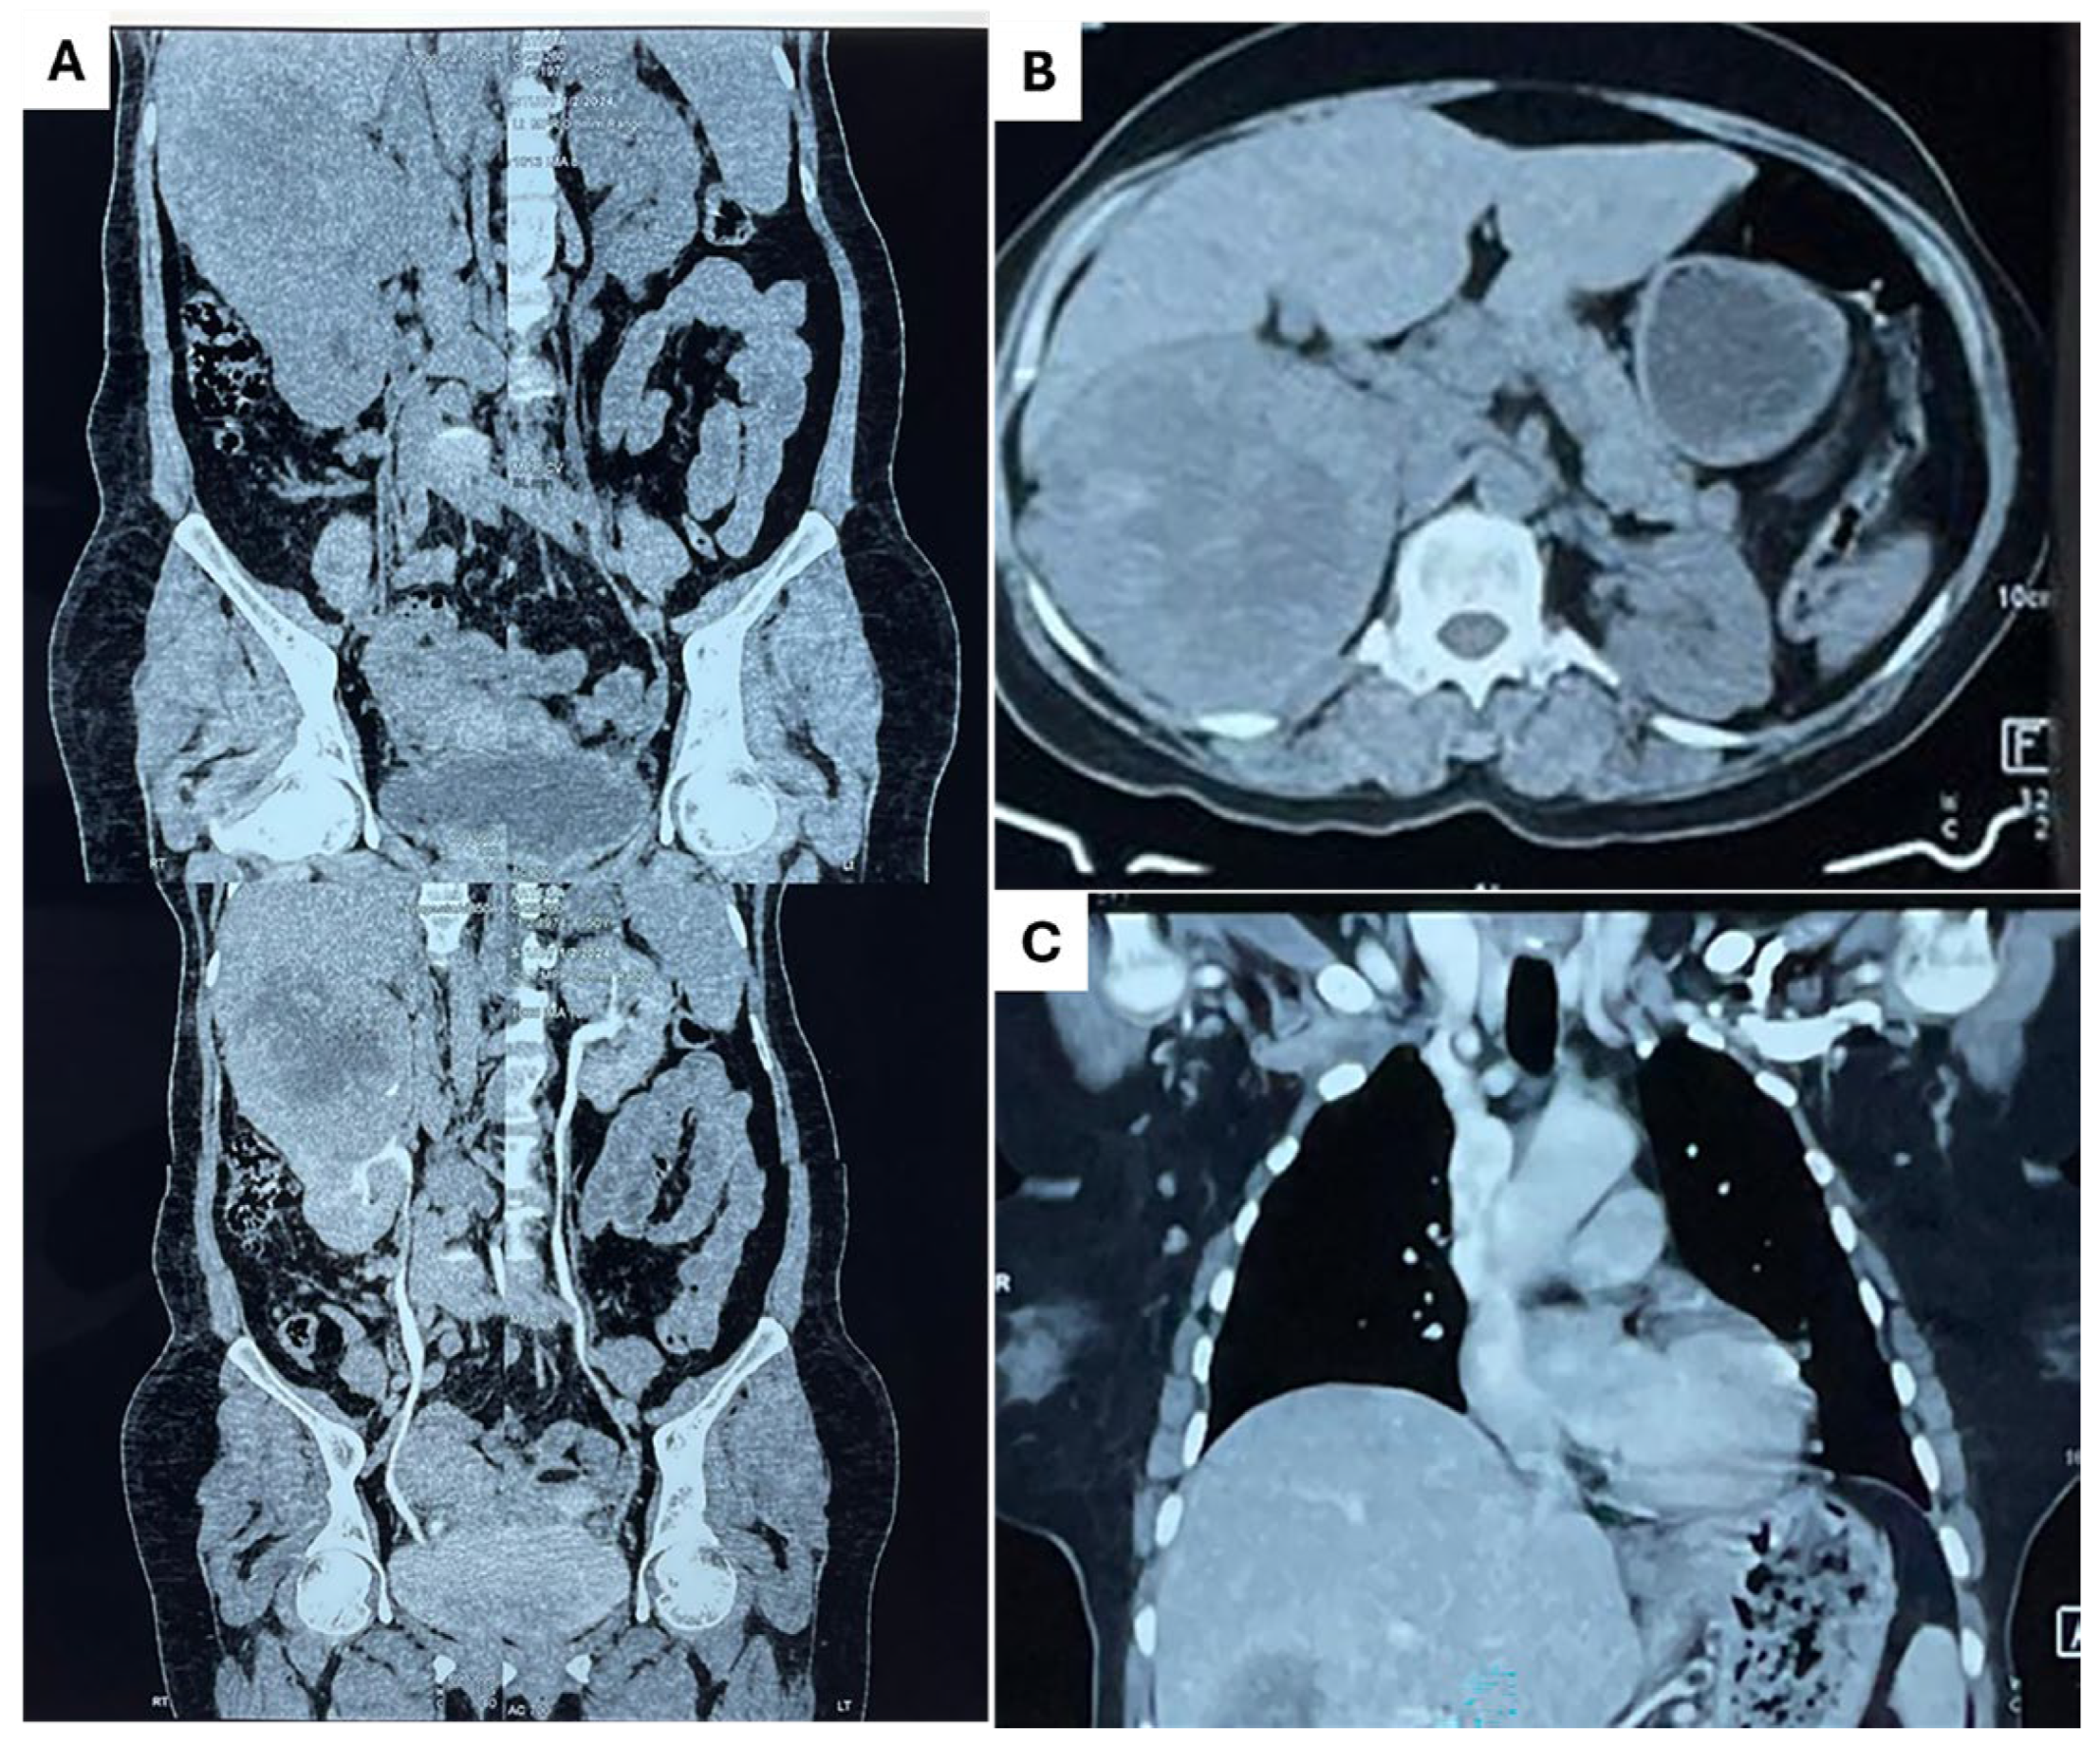

2. Detailed Case Description

| Habiba et al. (present study) | Buccal and palatal mucosa | F | 50 | Yes | Lung, adrenal gland, bone |